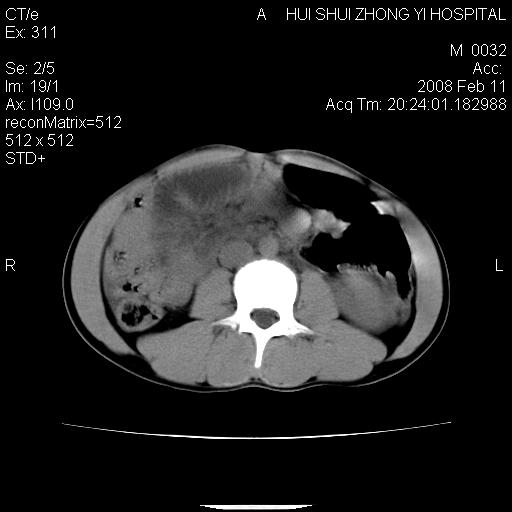

标题: CT11660:男,16岁,现腹痛剧烈,现发烧、头痛、恶心呕吐 [打印本页]

标题: CT11660:男,16岁,现腹痛剧烈,现发烧、头痛、恶心呕吐

8年前曾在贵洲省人民医院b超诊断为肝内胆管结石。现腹痛剧烈,现发烧、头痛、恶心呕吐县医院b超示胆囊肿大大小159*46mm,囊内见6*5mm强回声光团,胆各总管内径56mm。提示:胆囊结石、急性胆囊炎、胆总管重度扩张。

胆囊结石.急性胆囊炎.重度胆管扩张.右侧胸腔少量积液,建议ct增强

考虑先天性胆管囊肿;胆囊增大并结石。右侧胸腔少量积液,建议ct增强。

caroli囊肿并囊内结石。胆囊增大并胆结石。典型!

先天性胆管囊肿,胆囊结石、胆囊增大,右侧少量胸腔积液。